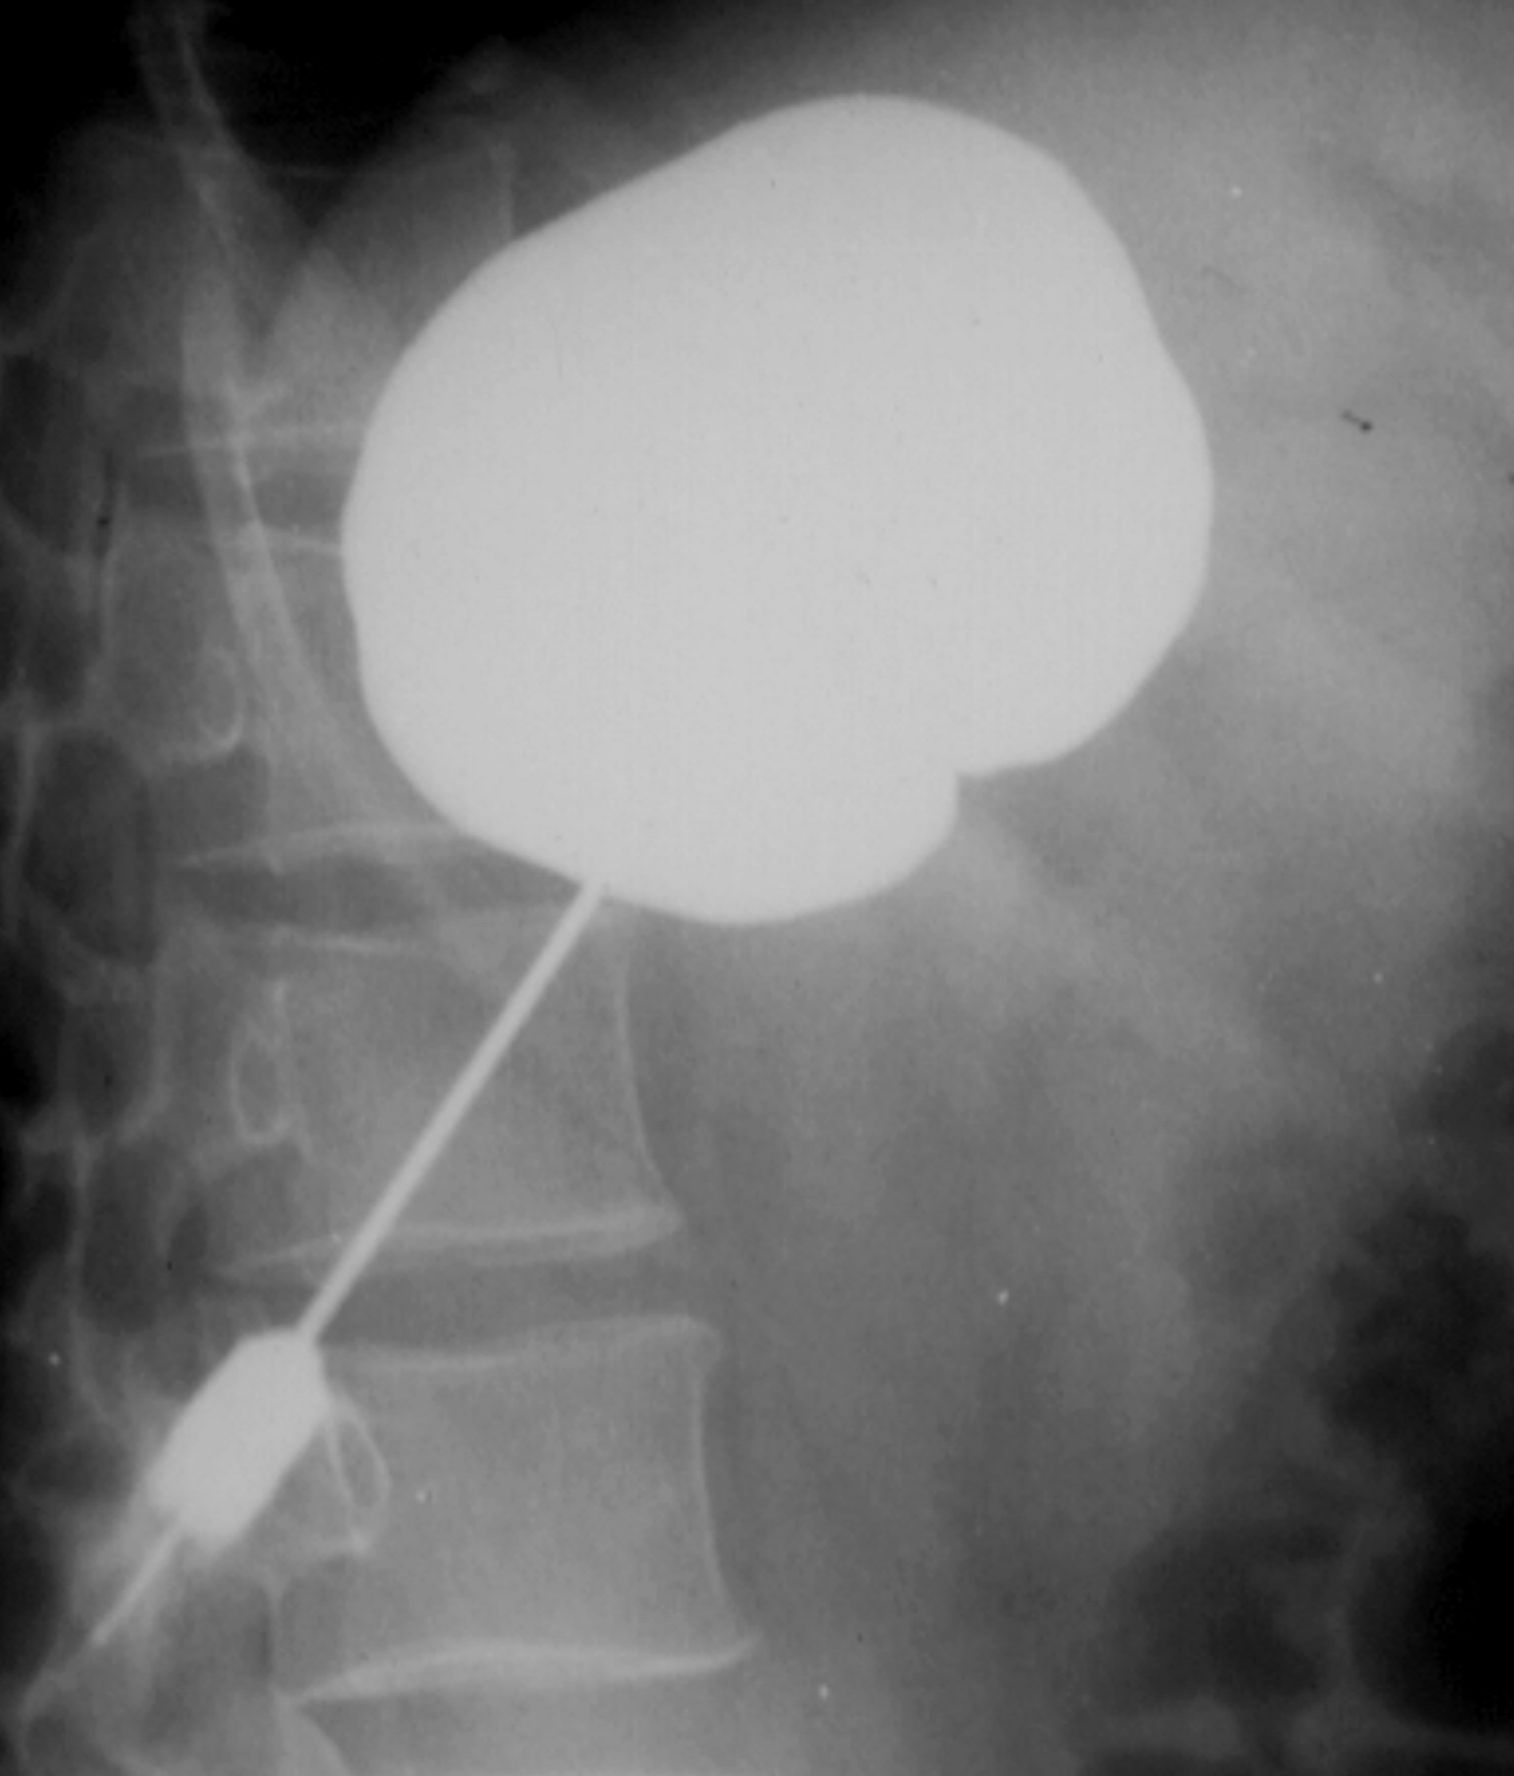

The most commonly performed intervention is US guided percutaneous nephrostomy. In special cases (obesity, visualization difficulties with US) CT guidance can also be chosen to create percutaneous nephrostomy. (Figure 30.)

Image

Figure 30. – Percutaneous nephrostomy contrast X-ray examination (CT guided catheter insertion)